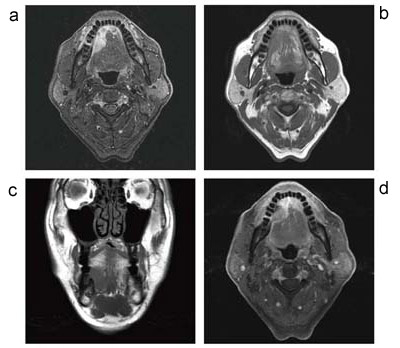

図5に,口腔底腫瘍の画像を供覧する。STIR,T1強調画像,CHESS法による脂肪抑制Gd-DTPAダイナミック造影画像であるが,画質はどれも申し分ないと思われる。CHESS法においても均一な脂肪抑制を示すあたりは,Discovery MR750の底力を感じる。

図5 口腔底腫瘍

a:STIR軸位断像 b:T1強調画像軸位断像

c:T1強調画像冠状断像

d:CHESS法による脂肪抑制T1強調画像軸位断像